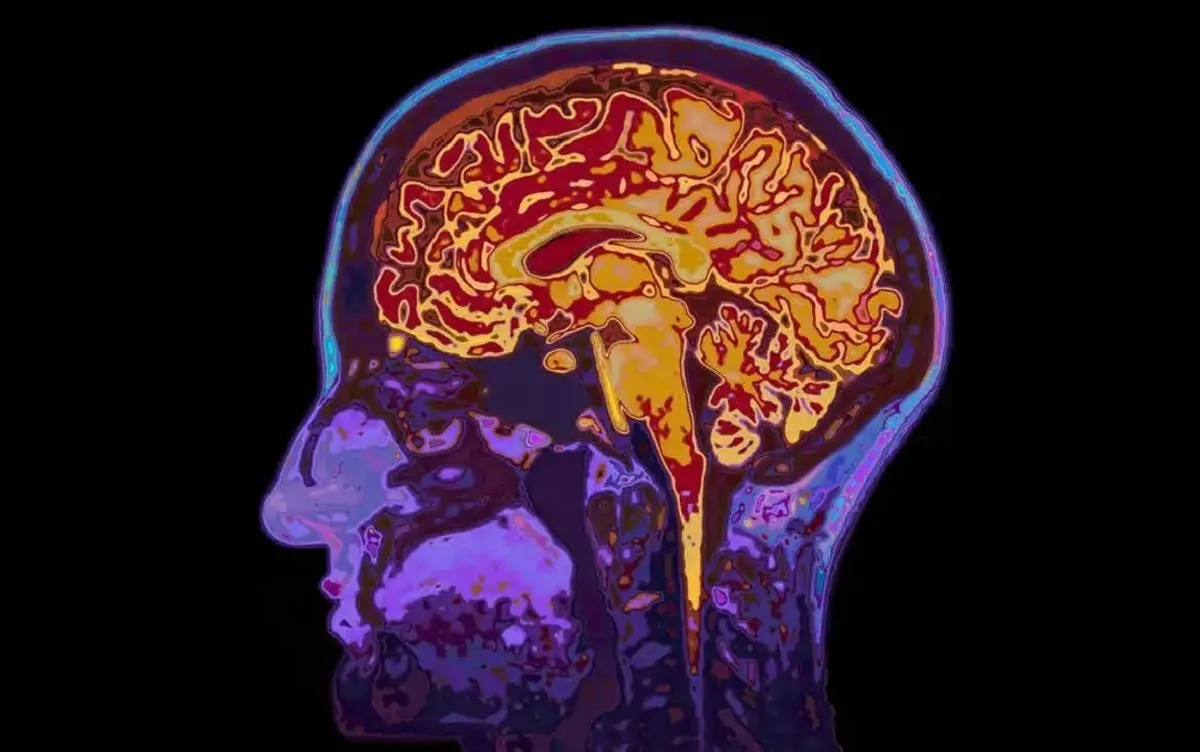

یک مطالعه تازه در سوئد نشان میدهد افرادی که خواب بیکیفیتی دارند، مغزشان در اسکنها پیرتر از سن واقعیشان به نظر میرسد.

به گزارش نیوزمدیکال، این مطالعه با مشارکت ۲۷ هزار و ۵۰۰ فرد میانسال و سالمند انجام شد که همه آنها امآرای مغز انجام دادند و متخصصان با کمک یادگیری ماشینی بر اساس بیش از ۱۰۰۰ شاخص امآرای، سن زیستی مغز آنها را تخمین زدند.